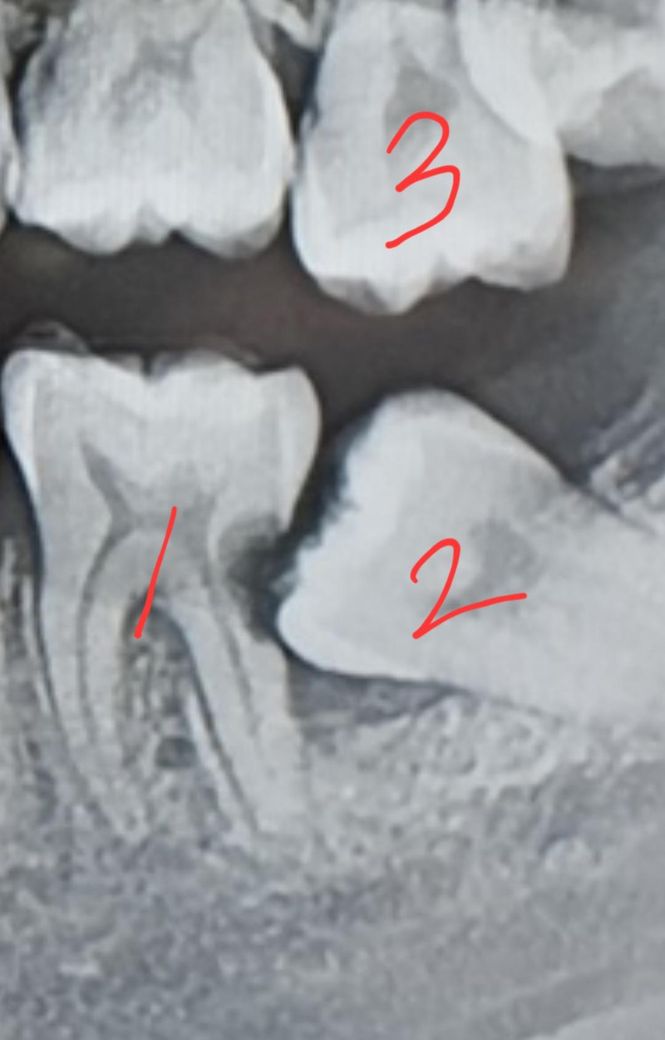

이 상황에 임플란트를 할지 크라운을 할지 너무 고민이 됩니다.

사진 속 아랫니는 둘 다 어금니 입니다...씹을 때 가장 중요하다는 두 치아가 모두 저 모양이죠...

치과에서 말하는 방법은 대부분 2번 치아 발치, 1번 치아 크라운, 3번 치아 크라운, 그리고 후에 2번 치아 자리에 임플란트입니다.

그런데 최근 가장 유명하고 규모가 큰 병원에 가보니, 1번 치아도 발치하고 임플란트를 권하더군요. 충치가 옆에 생겼기 때문에, 크라운을 해도 정말 몇일만에 못 쓸 수도 있을 것 같으니 임플란트가 맞는 것 같다고요.

느껴지는 증상으로는 틈 사이에 음식물이 낄 때만 약간의 통증이 있고 시린 증상이 있는데요. 전혀 흔들림도 없고 사실 안쪽 충치다보니 직접 보면 전혀 문제 없어 보여요... 그래도 1번 치아도 발치를 하고 임플란트...가 맞을까요? 크라운을 해도 못 쓸 가능성이 높을까요?

사진에 보이는 1.2번 치아는 발치를 하시고 나서 임플란트를 하시는게 좋을것같습니다. 사랑니 떄문에 앞치아가 많이 썩어서 발치를 하셔야될것같습니다.

사랑니는 기울어져 있고 앞에 치아의 충치를 유발할 수 있기 때문에 발치를 해야 되는 것이 맞습니다. 하지만 사랑니 앞에 있는 치아는 충치를 치료하고 신경치료를 하고 나면 충분히 사용을 할 수 있습니다. 가능하면 자신의 치아는 뽑지 않고 치료를 해서 사용할 수 있도록 하는 것이 좋습니다.

임플란트가 필요할 것 같습니다. 치아가 누우면서 해당 치아의 뿌리가 너무 약해졌습니다.